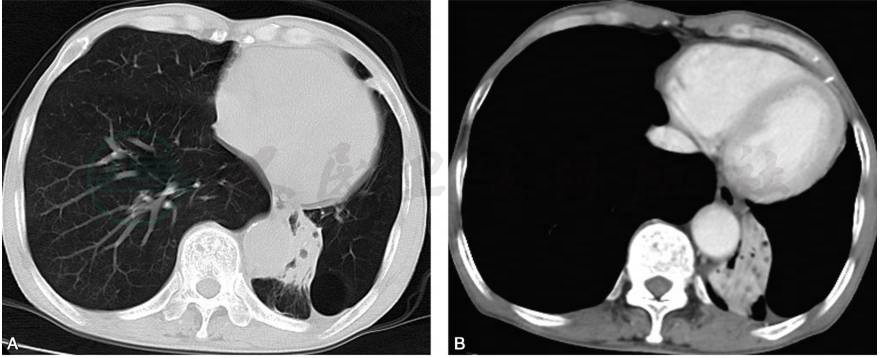

胸部CT检查(2017-03-29):双侧肺气肿,散在肺大疱;左肺下叶肺不张,纵隔左偏(图1)。

图1 胸部CT检查

A.双肺透光度增加,左肺容积明显减小,下舌段肺大疱,左肺下叶肺不张;B.纵隔左偏,左下肺不张